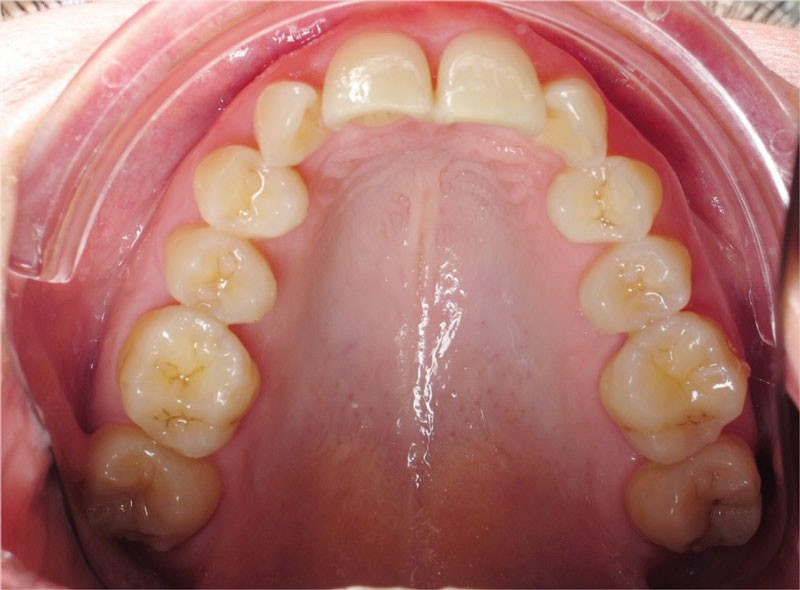

Un appareillage Damon métal a été mis en place, réalisé à partir d’un set up numérique Insignia pour obtenir un contrôle précis des torques et de la forme d’arcade et réduire le temps de finition grâce à un collage indirect très précis.

De larges surélévations postérieures étalées ont été mises en place et la patiente a porté des élastiques précoces suivant les principes de la technique Damon. Les 14 et 24 rempliront le rôle des 13 et 23.

L’objectif, en utilisant la technique Insignia est de réduire le temps de traitement de 28 à 18 mois avec 12 rendez-vous (fig. 5 à 14).